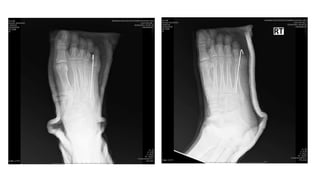

Investigation : Film Rt. foot AP/Oblique

Impression

• Open fracture Rt. 4th-5th metatarsal bone ( Grade II )

Investigation : FilmRt. foot AP/Oblique

• 12.

Impression • Open fractureRt. 4th-5th metatarsal bone ( Grade II )